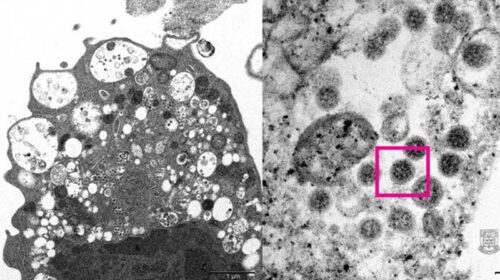

Вчені з Гонконгу отримали перше мікроскопічне зображення штаму COVID-19 Омікрон. Дослідникам вдалося зробити фото ураженої клітини нирки мавпи, повідомляють на сайті медичного факультету Гонконгського університету. Як пояснили вчені, при збільшенні фото на лівій частині можна побачити набряклі везикули – внутрішньоклітинні компоненти, які містять маленькі чорні частини вірусу. Праворуч на світлині можна роздивитися агрегати (інфекційні фрагменти) вірусних частин з шипами у формі корони на поверхні. Напередодні дослідники кафедри мікробіології Гонконгського університету повідомили, що їм вдалося відокремити штам Омікрон з клінічних зразків. Це може дозволити розробити та випустити вакцини проти нового варіанту…